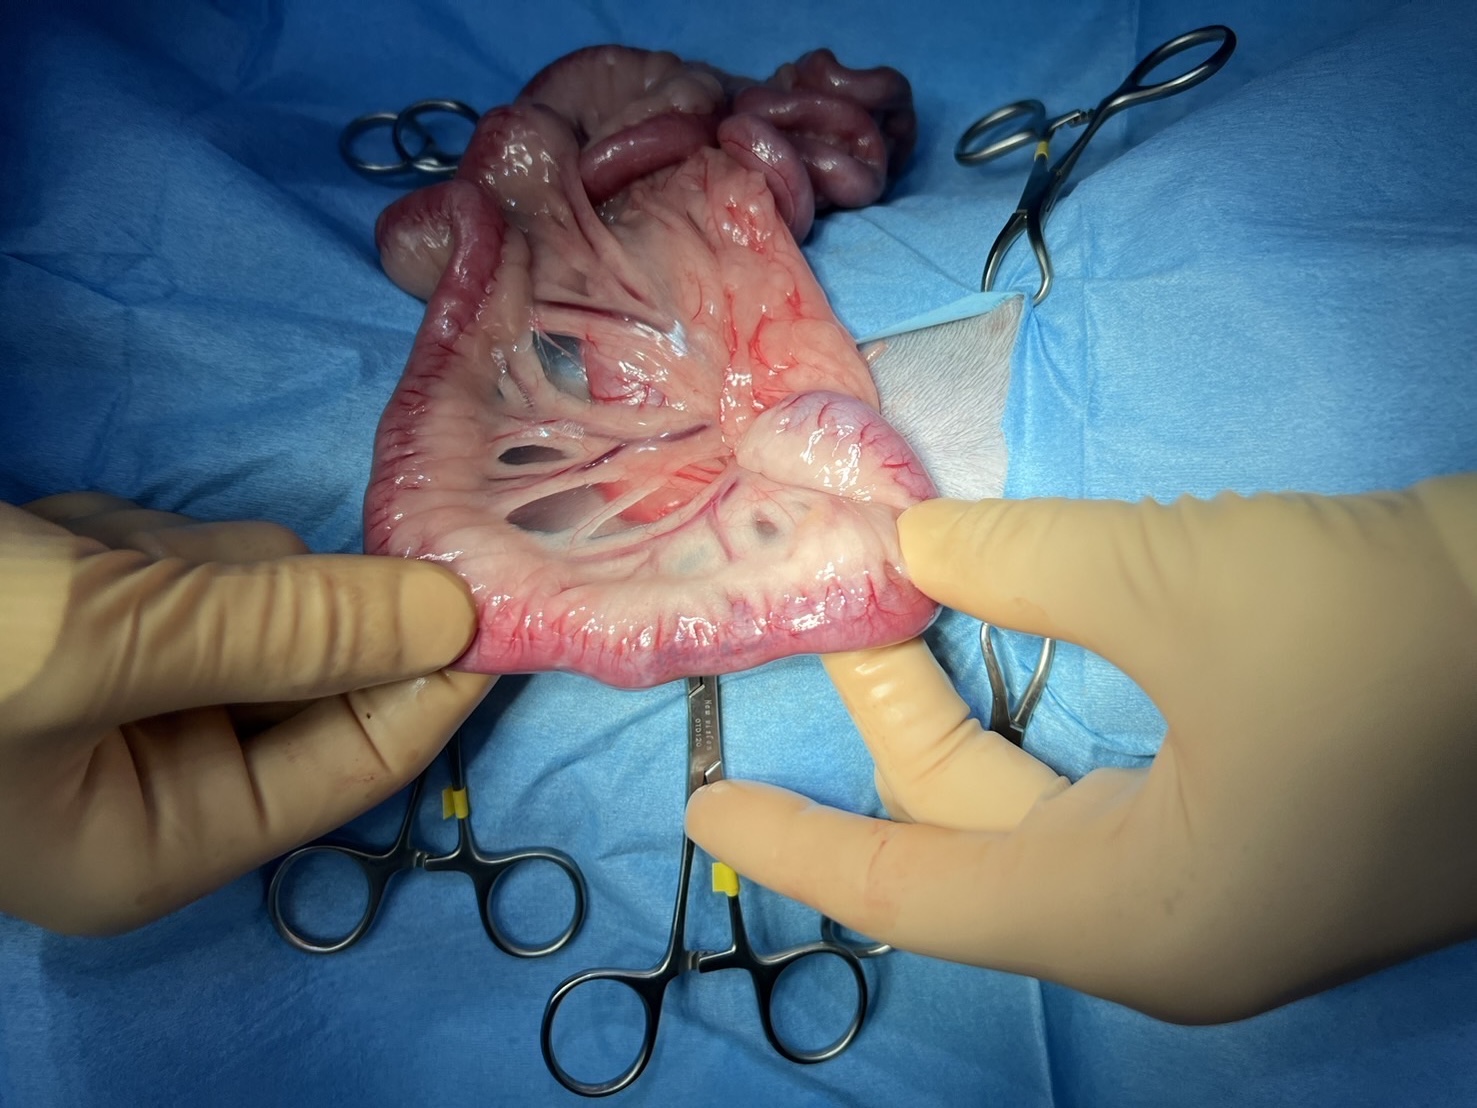

【手術画像】

空腸領域に閉塞物を見つけ、直上をメスで切開し異物の摘出を実施いたしました。

摘出された異物は毛糸やフェルトなどで構成されているようなもので、やや硬く、腸管を完全に閉塞させる大きなものでした。

術後3-5日に程度縫合した腸の裂開のリスクがあるため注意が必要です。